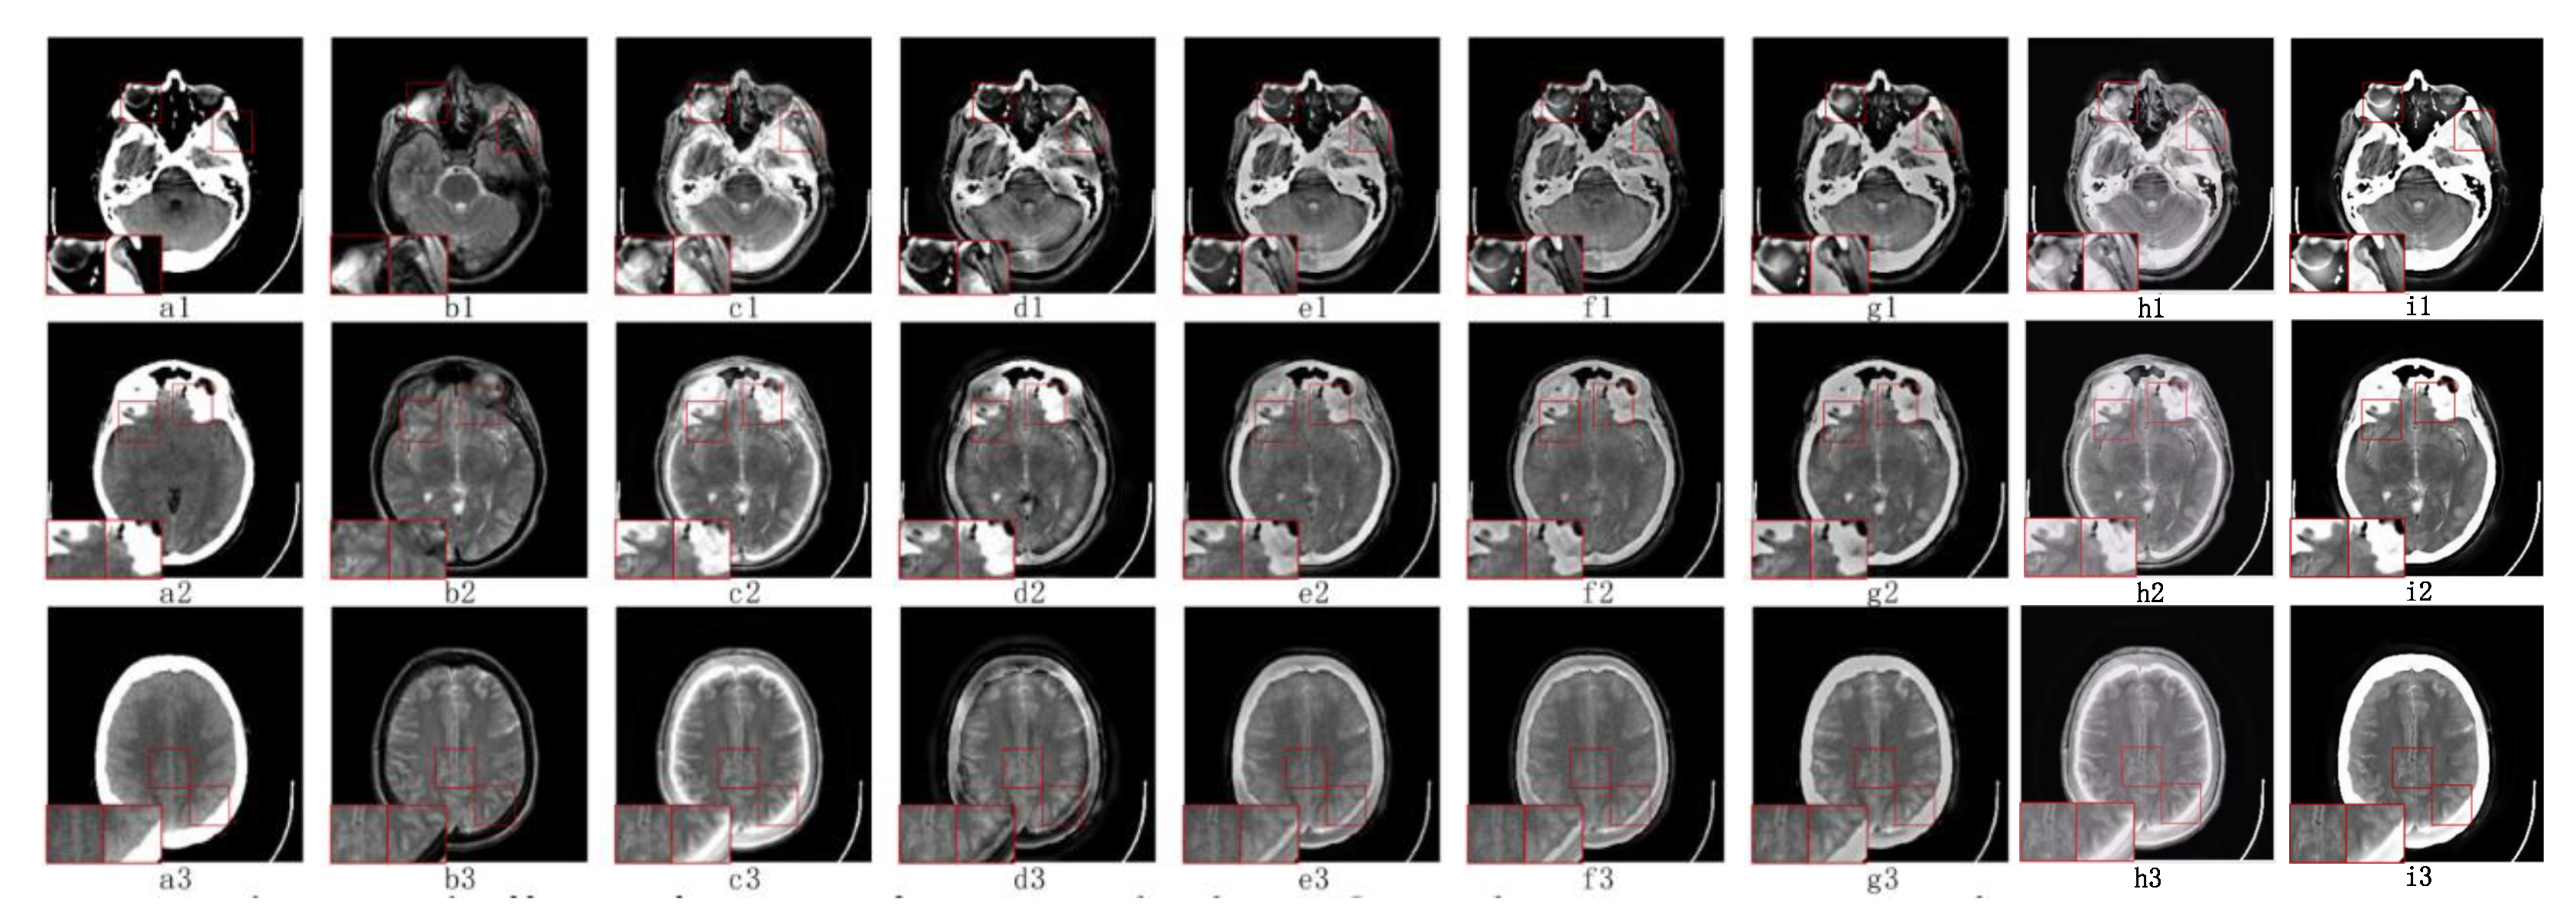

5.2.1. Fusion Analysis on T1-T2

5.2.2. Fusion Analysis on T2-PD

5.2.3. Fusion Analysis on CT-MRI

5.2.4. Fusion Analysis on MRI-PET

5.2.5. Fusion Analysis on MR-SPECT